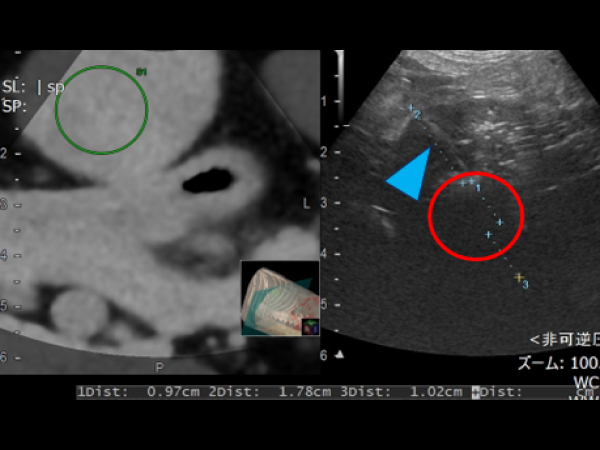

内側左葉に36.2×45.1㎜の腫瘤が認められ、ツルーカット生検で肝細胞癌と診断されました。 摘出も可能でしたがもともと肝臓が小さく肝機能が低下しているため負担の少なさを考慮してフュージョンイメージングを用いてアブレーションを実施しました。 症例②と同様に肝臓腫瘍の周囲に生理食塩水を満たして実施しました。 術後は合併症もなく翌日元気に退院しました。摘出手術を行うよりも麻酔時間の短縮や術後の経過が良好でした。

フュージョンイメージング

アブレーションする範囲を緑丸のようにガイドをつけることも可能

フュージョンイメージングのガイドを用いてアブレーションを実施

アンテナ(青矢頭)と焼灼されているところ(赤丸)

アブレーション後の超音波画像